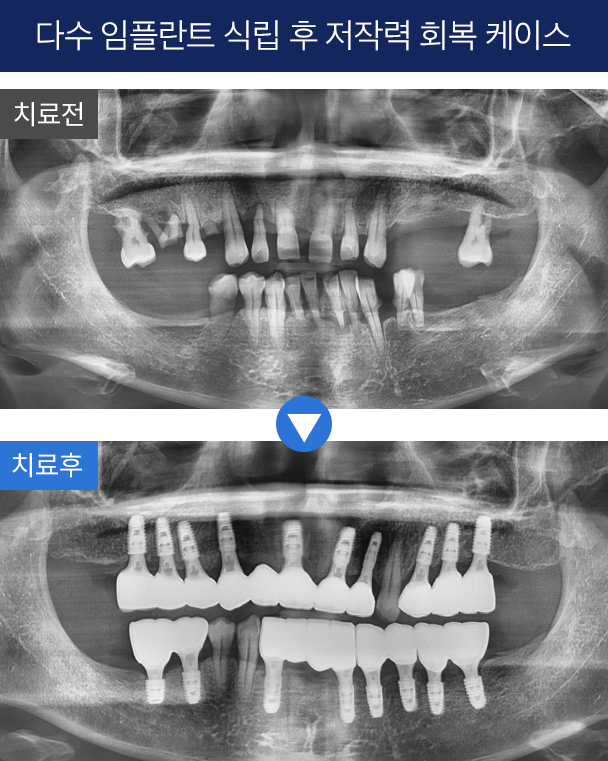

1